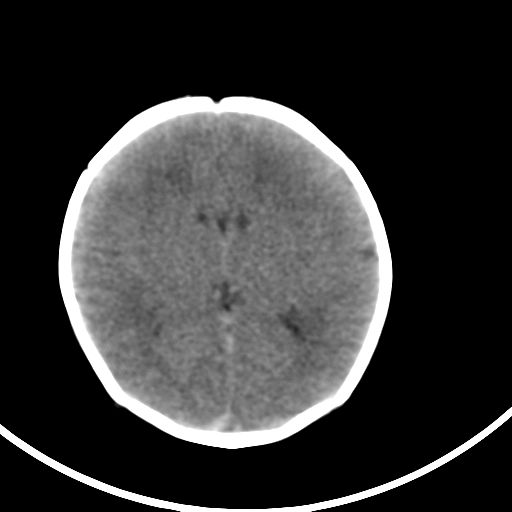

新生儿3天,超过预产期5天剖宫产,有缺氧病史,具体评分不详,现反应差,肌张力低,前囟平,原始反射存在,无苦闹等。

kaolv小脑幕,后纵裂区蛛网膜下腔出血;轻度脑肿胀

矢状窦旁征——支持蛛网膜下腔出血